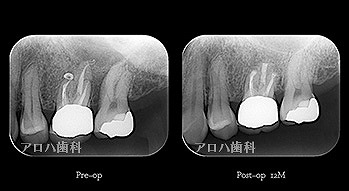

case4

再根管治療 2年予後

再根管治療の汚染の改善

破折器具除去もあり。